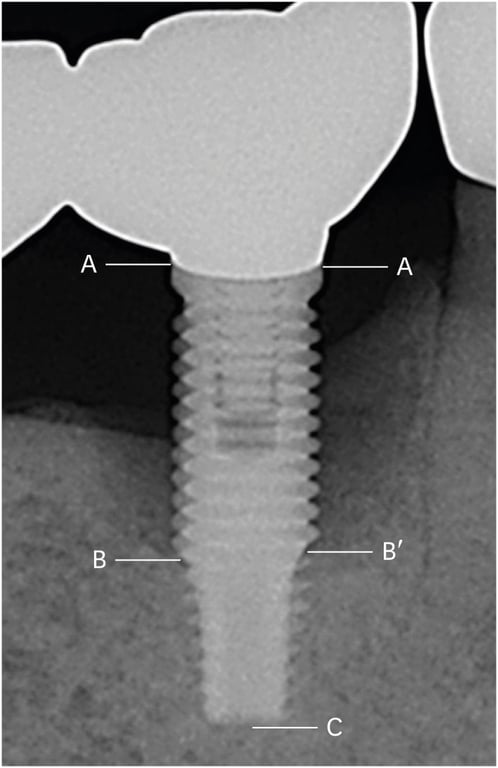

Figure 1. A representative radiographic view at the baseline day (A) and the endpoint (B).

Figure 2. The distance from the implant shoulder to the most coronal bone-to-implant contact point (DIB) was measured at the mesial and distal aspects of each implant: A, implant shoulder; B and B′, the most coronal bone-to-implant contact point; C, apex of the implant fixture; A–B, DIB at the distal aspect; A–B′, DIB at the mesial aspect; and A–C, length of the implant fixture (on radiographic view). Amount of actual marginal bone loss at the mesial and distal aspects (X′ and X) calculated follow as:

X′=(A–B′)×fixture length (actual)/(A–C) X=(A–B)×fixture length (actual)/(A–C)